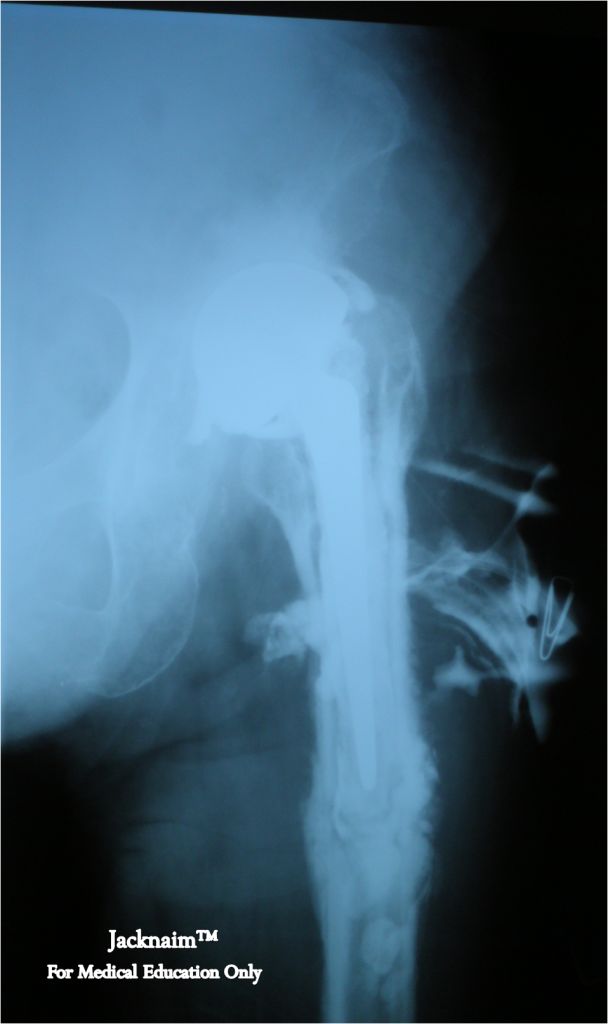

From jacknaimsnotes.blogspot.com

My Medical Notes Bone infection Arm Bone Infection This may occur under a skin sore. Osteomyelitis is a bone infection that happens when bacterial or fungal infections spread from other parts of your body into your bone marrow. It usually goes away if treated early with antibiotics. In adults, osteomyelitis can be either acute or chronic. This type is most common in infants and. Osteomyelitis is a painful. Arm Bone Infection.